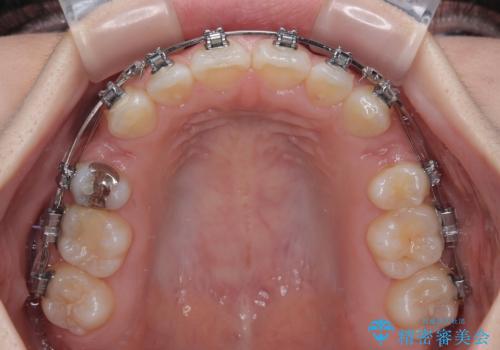

- 矯正装置

- メタルブラケット

- 治療期間

- 2年2ヶ月

- 治療回数

- 10-30回